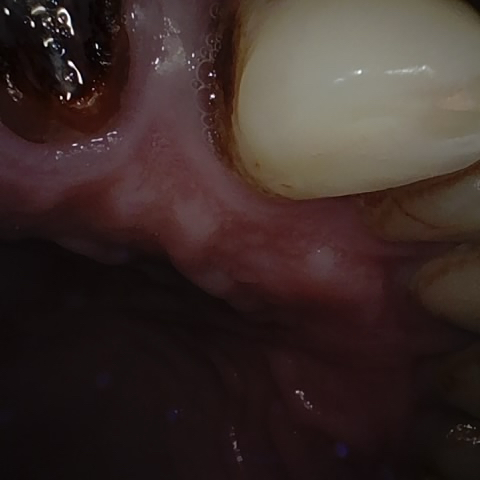

Annotated as "Good"